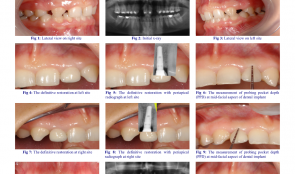

MANAGEMENT OF CONGENITALLY MISSING LATERAL INCISORS WITH ORTHODONTICS AND SINGLE-TOOTH IMPLANTS

approach. Dental implants are an appropriate treatment option for replacing these teeth in adolescents when their dental and skeletal development is complete. This case report describes the orthodontic treatment of a patient with permanent dentition who had congenitally missing maxillary lateral incisors. After orthodontic treatment, the missing incisors were replaced with implants. Methods: A 21-year-old woman with congenitally missing maxillary lateral incisors was referred to our clinic. Her medical and dental history was evaluated. The treatment plan included orthodontic treatment and space opening for implant placement and correction of the occlusion. Results: The major objectives of treatment were achieved. Molar and canine class I relationships were achieved with overjet and overbite within the normal range. Panoramic radiographs showed good radicular parallelism and no signs of root resorption. Dental implants were placed in lateral incisor sites. Conclusions: Dental implants are the treatment of choice for most patients with congenitally missing lateral teeth. The preserve tooth structure and alveolar bone and provide aesthetics and function. However, successful restorative treatment involving implants depends on interdisciplinary treatment planning, especially if preprosthetic orthodontic tooth alignment is required. -